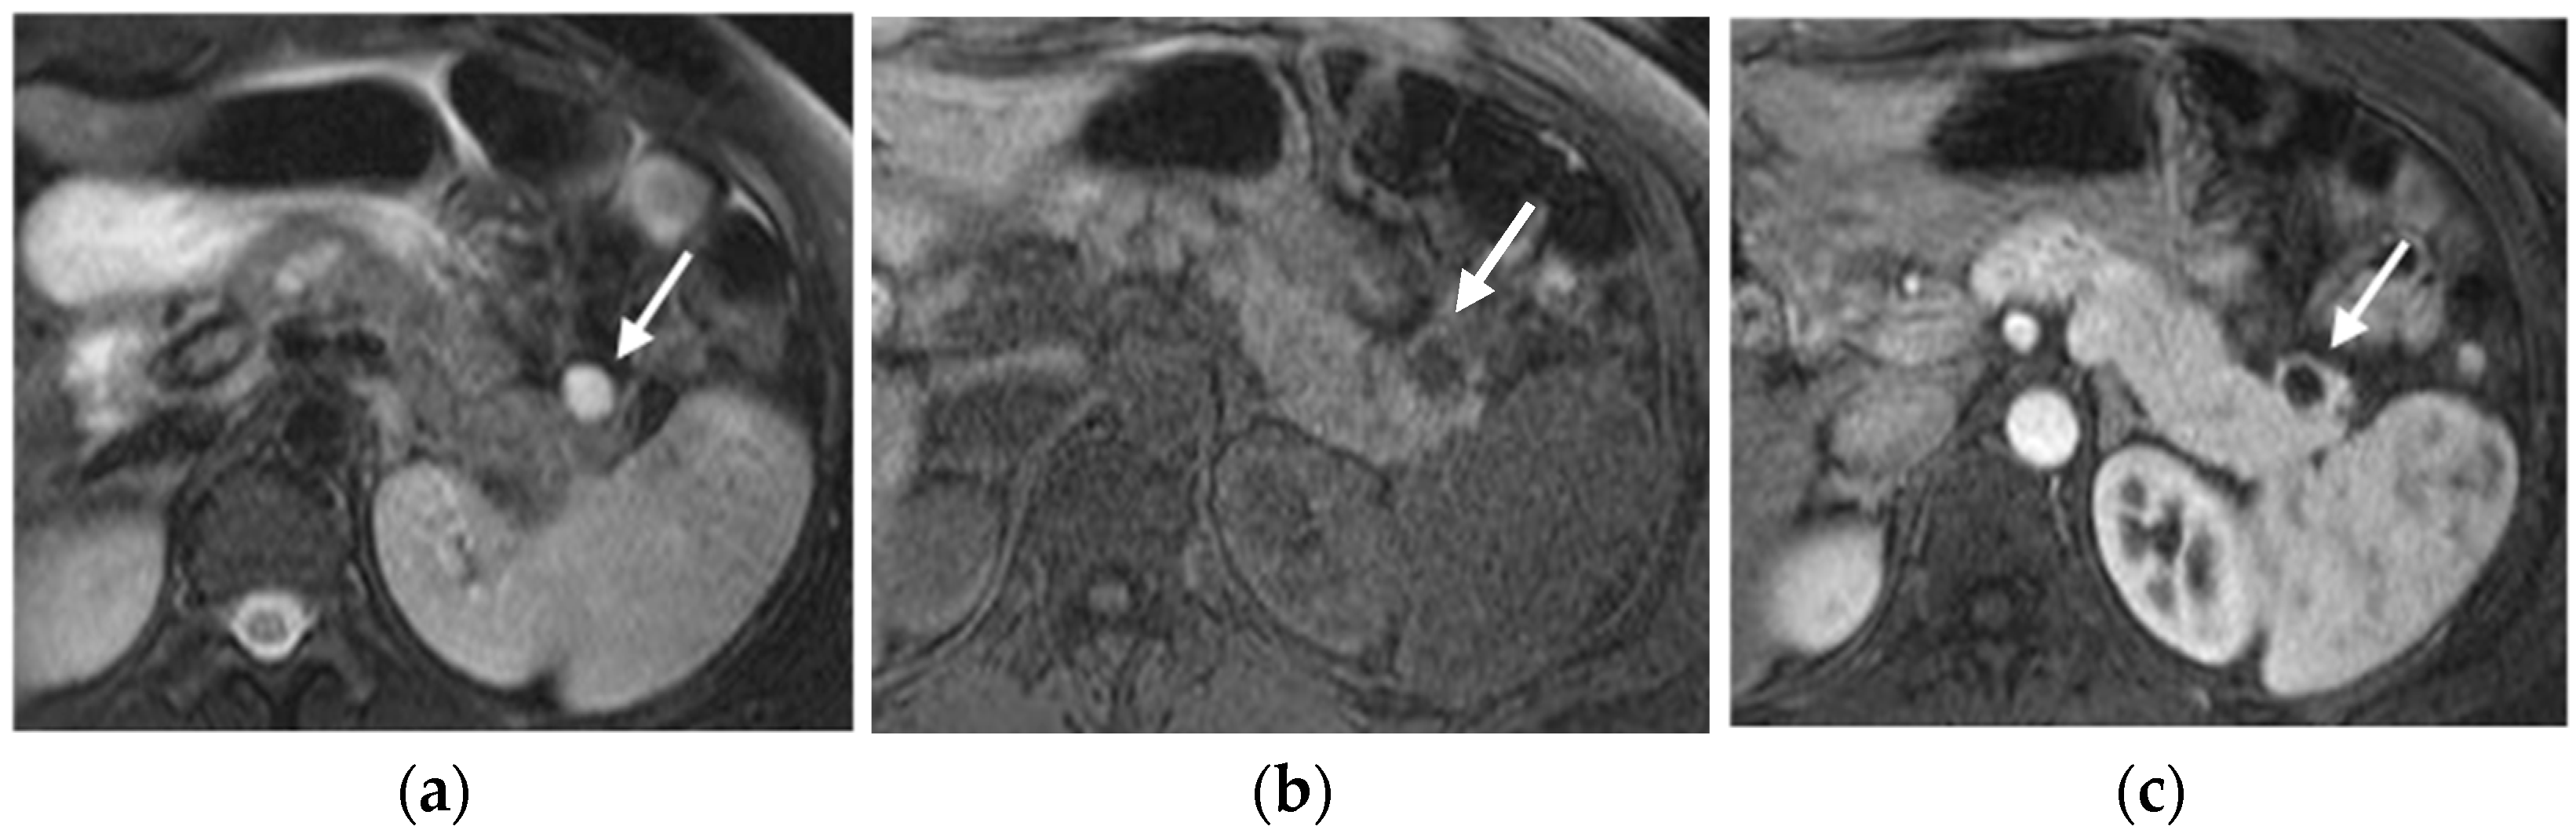

The specific MRI appearance of PNETs can be influenced by factors such as tumor grade, size, and the presence of cystic or necrotic areas within the lesion [40] (Figure 5).

Figure 5.

Cystic pancreatic NET of the tail (arrows). Fat-sat T2-weighted image (a) and T1-weighted image (b) show a cystic-like lesion in the pancreatic tail with a thick and irregular enhancing wall (c,d). PET-CT highlights high tracer uptake of the lesion (e). In the same patient, ultrasound revealed a synchronous parathyroid adenoma (f).

Compared to the surrounding pancreatic tissue, pNETs usually appear isointense/hypointense on T1-weighted MRI sequences and variably hyperintense on T2-weighted MRI sequences, depending on the amount of collagen in the tumor [32].

PNETs exhibit varying signal intensity with Diffusion-Weighted Imaging (DWI), but they often demonstrate restricted diffusion, with smaller lesions potentially being not easily detected on other MRI sequences [17]. Less differentiated tumors demonstrate even more diffusion restriction (Figure 6).